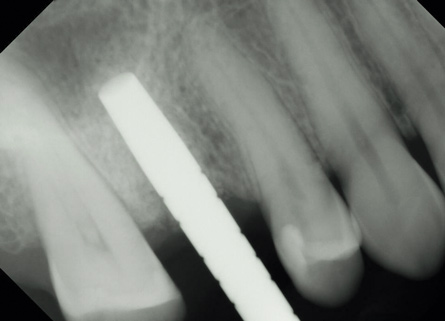

(6.) Osteotomy created with implant drill, stopping 2-mm short of the crestal height to avoid damage to the sinus membrane.

Figure 6

(7.) Radiograph of the osteotome in the site to verify depth in relation to the sinus floor with needed sinus elevation height.

Figure 7